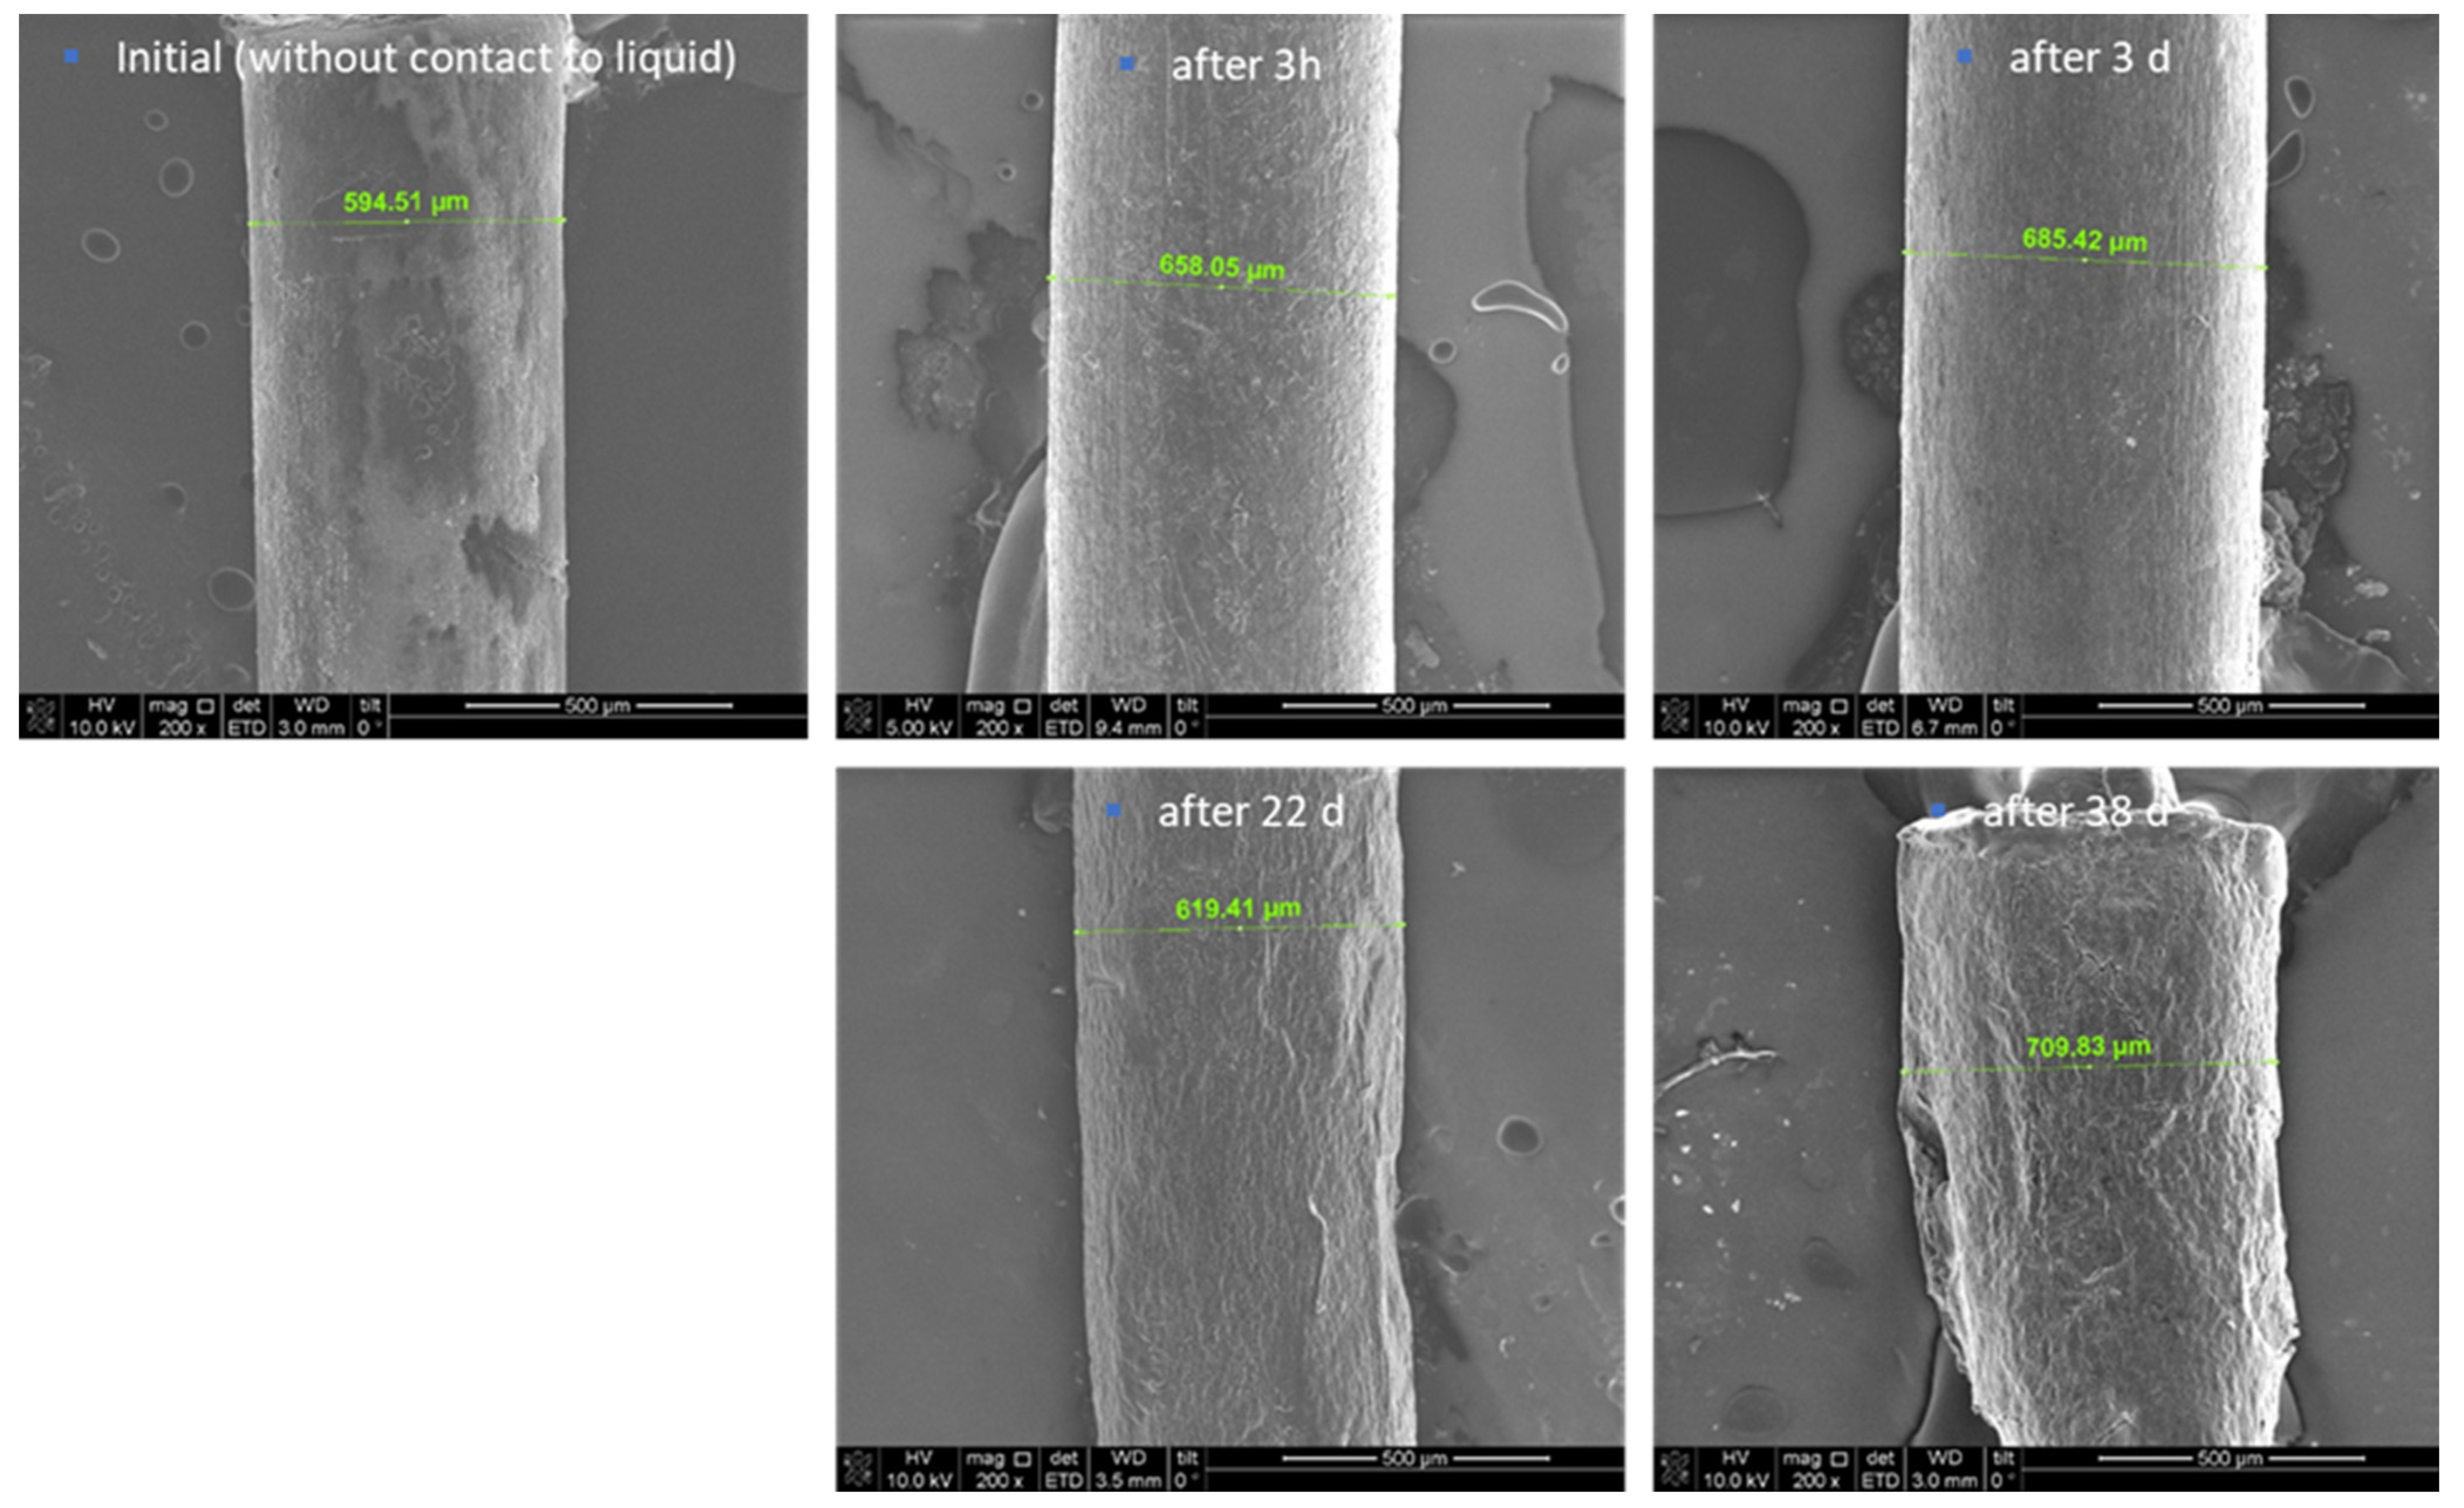

The swelling behaviour and degradation of the MIN-T extrudates were investigated while storing them in phosphate buffered saline (PBS) at 37 °C for up to 38 days.

The swelling behaviour (increase in volume and size) was followed for 11 days by using laser scanning microscopy (LSM). Thereby, the highest increase in volume was observed after 3 days. The measured volume enlarged by more than 40% compared to the starting volume, leading to an increase of the radius from approx. 600 µm to approx. 660 µm. Between days 4 and 11, the volume of the thread remained relatively constant which corresponds to an increase in the volume of nearly 30% compared to the original volume (Figure 1).

Furthermore, scanning electron microscopy (SEM) images were depicted and used for the description of the degradation behaviour of the formulation. Thereby, the initial state of the formulation is characterized by an inhomogeneous, partly rough surface (Figure 2). Structures with crystallite-like shapes are clearly visible. This finding can be explained by the included magnesium stearate of the MLC, which is known to form such surface structures. Again, an increase in the thickness of the thread and thus a clear swelling was determined after 3 h and 3 days in PBS, respectively. Even after 22 days the thread diameter was still larger compared to the initial situation; however it was smaller than after 3 days. A possible explanation might be that fragments start to detach from the surface, which is underlined by the detection of small amounts of magnesium stearate in the daily exchanged PBS. The ongoing degradation results in the formation of very small pieces, so after day 38 it was not possible to generate samples for further investigation of the process.

At higher magnifications (Figure 3), cracks and break-off edges were visible starting on day 22, which are hints for the progressing dissolution and degradation process. A porous network structure became more and more visible after a prolonged storage time in the buffer. As described above, after 38 days, the polymer extrudate was broken into several smaller pieces. Analysis of the pieces suggested a repeated swelling on the one hand but, on the other hand, the fact was that PBS was not penetrating through the complete extrudate before. After 38 days, ongoing storage of the formulation was stopped due to its progressing degradation, which made it impossible to further investigate the process.

4.2. In Vitro Swelling and Degradation Studies

The swelling behaviour and degradation of the formulation were investigated on the extrudates. For the latter experiments, the extrudates were stored in PBS (pH 6.8, 4 mL) without light exposure at 37 °C for up to 38 days under slight shaking (80 rpm). The extrudates were observed by a laser scanning microscope (LSM) or a scanning electron microscope (SEM) before and after different exposure times.

The swelling behaviour of the threads was documented by a laser scanning microscope (VK-1000/1050, Keyence Germany GmbH, Neu-Isenburg, Germany) before experimentation, and after 2, 3, 4, 7, 9 and 11 days, respectively. These time points were chosen according to pre-studies. After day 4, no further swelling was observed, and the experiment was finished on day 11. Samples were taken out at each time point from the PBS buffer, immediately investigated by LSM, and placed back into the PBS buffer. The volume increase of the thread was calculated by image evaluation software (Multifile Analyzer, Keyence, Germany GmbH).

Further, the surface morphology of the extrudates was documented before experimentation, after 3 h, and then after 3, 22, and 38 days, respectively, by SEM (Quanta 3D FEG from FEI company). One sample was taken out at each time point from the PBS buffer and immediately prepared for investigation using SEM analysis. Samples were prepared using Nanosuit technology (NanoSuit® from NanoSuit Inc., Hamamtsu, Japan) to obtain a conductive layer on the surface. The following magnifications were used: 200× and 10,000×.

Figure 2. SEM images of the extrudates before, after 3 h, 3 d, 22 d, and 38 d of storage in PBS, 200× magnification.

Figure 3. SEM images of the extrudates before, after 3 h, 3 d, 22 d, and 38 d storage in PBS, 10,000× magnification.